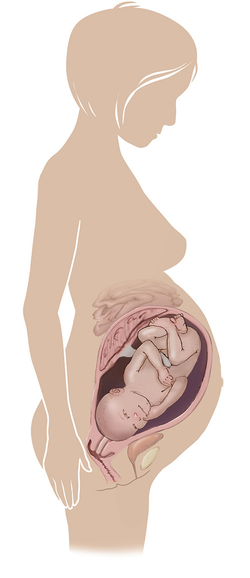

مراحل تطور الجنين أثناء الحمل

تطور الجنين خلال فترة الحمل على ثلاثة مراحل: أول 14 أسبوع من الحمل ، ثم تطوره بداية من الأسبوع 14 وحتى 28 أسبوعا ، ثم الثلث الأخير من 28 إلى 40 أسبوع من الحمل ... المزيد

مراحل تطور الحمل أسبوعيا بالصور

مراحل تطور الحمل أسبوعيا لكل من الأم والجنين داخل الرحم مدعومة بالصور التوضيحية ... المزيد